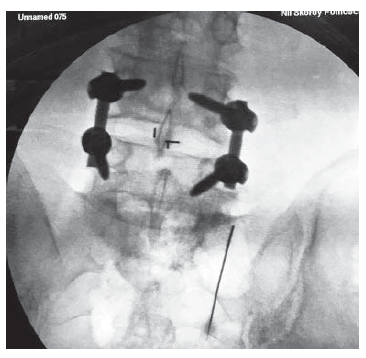

В наших случаях у пациентов, перенесших различные виды оперативных вмешательств по поводу ДДЗП, показанием к выполнению ВЧДМС считали наличие спондилоартроза смежных сегментов, не дошедшего до стадии деформации сустава и не вызывающего стеноз позвоночного канала. Денервация выполнялась на стороне преобладающего поражения суставов или с двух сторон. Под рентгенологическим контролем по костным ориентирам к иннервирующим суставы возвратным веточкам спинномозговых нервов подводили иглы-порты (рис. 2) и выполняли обработку нервов током высокой частоты по установленной методике. После выполнения процедуры высокочастотной денервации у 80% пациентов получен положительный результат в виде снижения болевого синдрома. В 17 наблюдениях в связи с возобновлением болей или преобладанием болевого синдрома с другой стороны была выполнена повторная процедура, полностью устранившая болевой синдром.

Рис. 2. Интраоперационные рентгенограммы при выполнении ВЧДМС